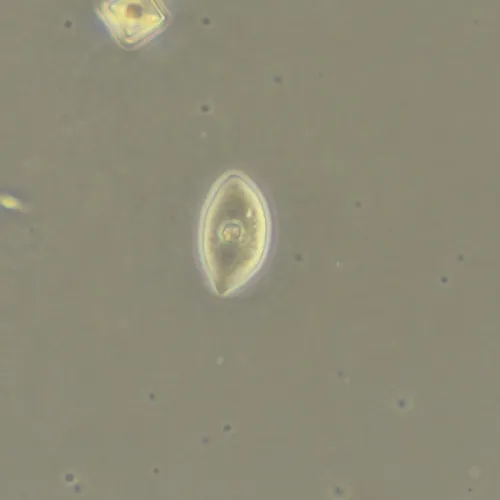

Фазово-контрастная микроскопия позволяет увидеть детали прозрачных образцов, которые практически не видны в светлом поле, и при этом не повреждать их окрашиванием. Метод применяют в разных сферах: медицине, биологии, ветеринарии, сельском хозяйстве, фармацевтике, экологии.

Оптика фазового объектива конструктивно дополнена фазовым кольцом в плоскости выходного зрачка. Фазовый объектив может работать и в фазовом контрасте, и в светлом поле, но в светлом поле демонстрирует не столь высокие результаты.